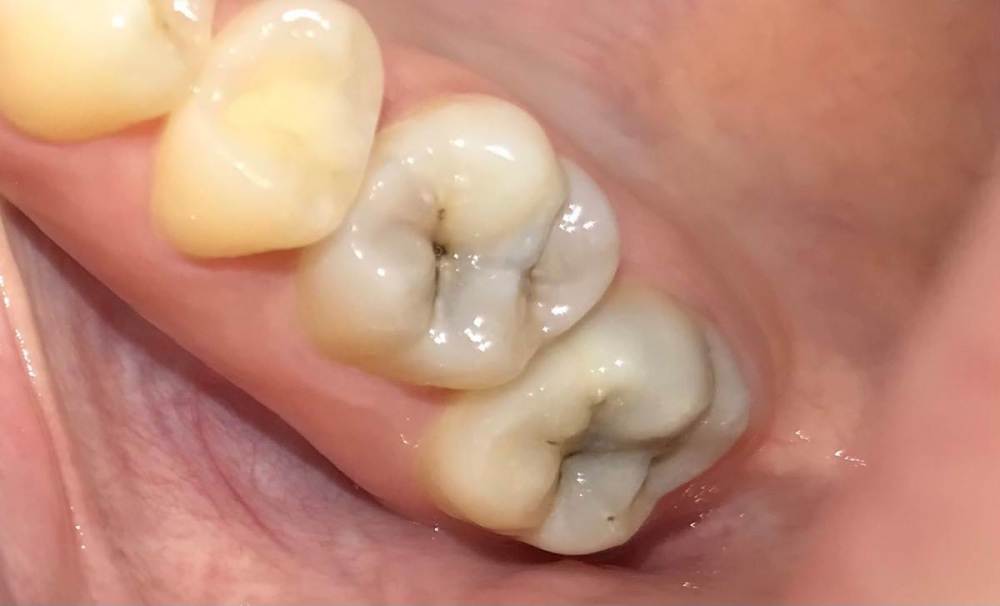

cryptiik Опубликовано 16 февраля, 2023 Автор Поделиться Опубликовано 16 февраля, 2023 @IvanK болеть - не болят, но кариес очевиден, думаю( Ссылка на комментарий

Carioznik Опубликовано 16 февраля, 2023 Поделиться Опубликовано 16 февраля, 2023 1 час назад, cryptiik сказал: кариес очевиден, думаю Уже, скорее, пульпит Ссылка на комментарий

IvanK Опубликовано 16 февраля, 2023 Поделиться Опубликовано 16 февраля, 2023 кариес точно есть, чем дольше ждете, тем ближе к пульпиту 1 Ссылка на комментарий

Carioznik Опубликовано 16 февраля, 2023 Поделиться Опубликовано 16 февраля, 2023 1 час назад, cryptiik сказал: по снимку? По снимку диагноз не ставится. Это лишь дополнительный метод исследования. Ваше фото, в данном случае, даже более показательно, чем этот снимок. По фото: точно видно, что в обоих зубах огромный кариес, а возможно уже и пульпит. Ссылка на комментарий